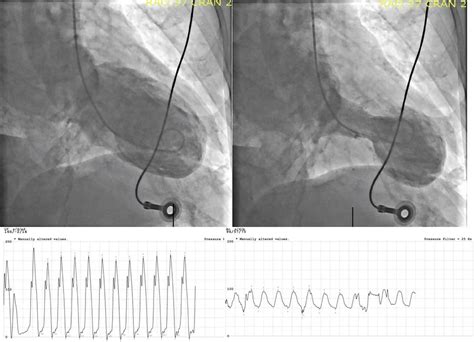

• Imaging: After the adenosine infusion, imaging techniques such as echocardiography or nuclear imaging may be used to visualize the heart and assess blood flow. These images help identify any areas of the heart that are not receiving adequate blood supply.